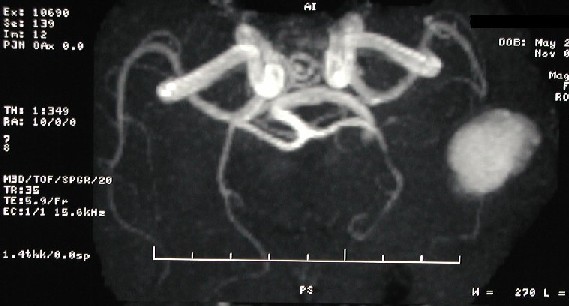

Kraniyal Magnetic rezonans anjiyografi (TOF-MRA technique) 'de sol temporopariyetal alanda yerleşmiş, göreceli olarak büyük boyutta, anevrizma görünümlü hiperintens alan izlenmektedir.

Tanı: TOF ("time-of-flight") MR anjiyografi (arteriyogram) 'de beyin içine kanama nedeni ile anevrizma gibi görülen anormal sinyal görülmektedir (MRA artefaktı).

1 - Akut-subakut kanama TOF-MR anjiyografide artefakt nedeni olabilir ve dikkat edilmez ise yanlışlıkla anevrizma tanısı konabilir. Bu artefaktın nedeni hematom içinde bunulan methemoglobin'in kısa T1 relaksasyon zamanının olmasıdır (TOF görüntülerinde hiperintens sinyale neden olur). Faz-kontrast MR anjiyografi'de bu hiperintens olarak görülmez (dolayısı ile anevrizma - artefakt ayırımı bu yöntemle yapılabilir). Bununla birlikte, her iki yöntem de (TOF ve Faz-Kontrast) de manyetik "susceptibility" etkisi nedeni ile (deoxyhemoglobin ve hemosiderin/ferritin etkisi ile) sinyal kaybolması görülebilir (bu da kısmen pıhtı ile lumeni tıkanmış anevrizmalarda patent olan lümenin görülmemesine neden olabilir).

Genel tıp uygulamalarında, bu sıkça görülen bir artefakt değildir. Dikkatli olarak tüm MR tetkikinin incelenmesi, ayrıca dikkatli bir hasta klinik hikayesinin irdelenmesi doğru tanı konulmasında önemli yer tutar.

Kanamanın MRG'deki intensitesi kanamanın ne zaman olduğuna bağlı olarak değişiklik gösterir. Yukarıda sunulan hastada, görülen beyin içi kanamanın sinyal özellikleri subakut kanama ile uyumludur.